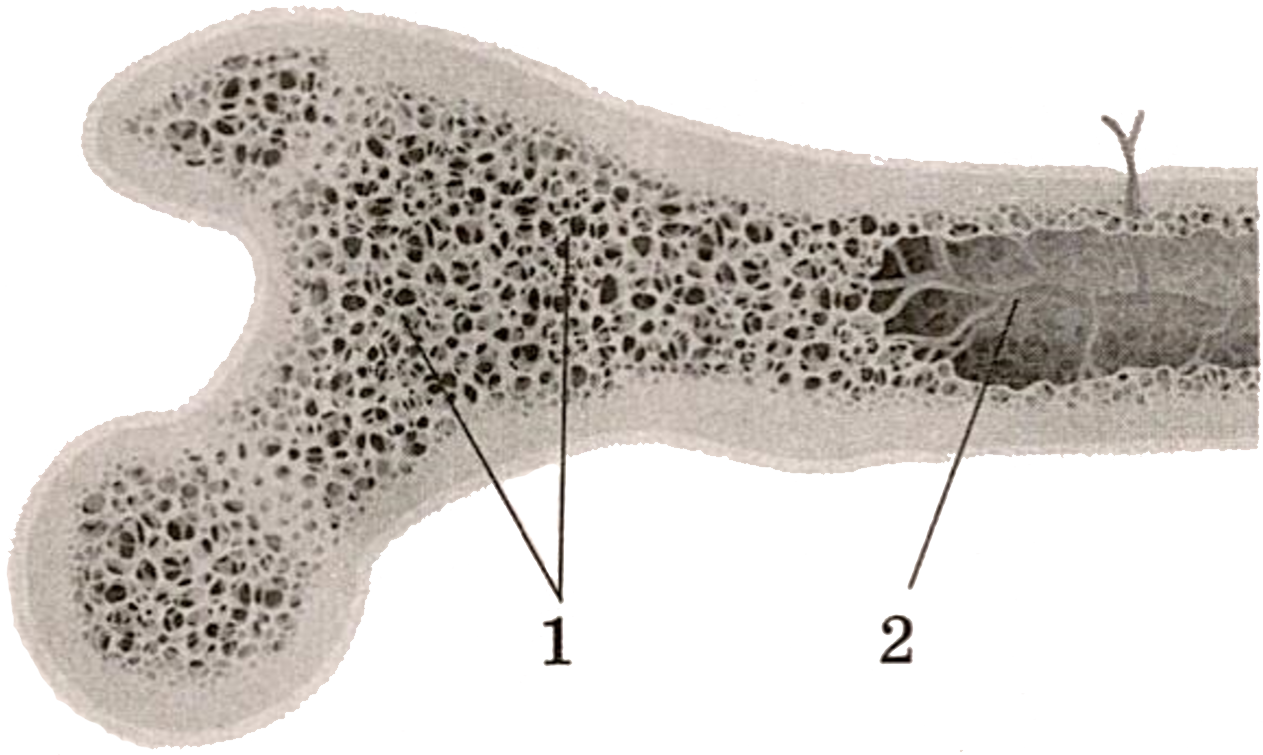

Структура грубоволокнистой костной ткани: наглядные примеры